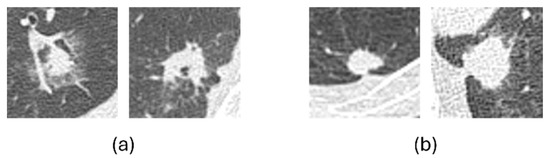

Preliminary Study on Image-Finding Generation and Classification of Lung Nodules in Chest CT Images Using Vision–Language Models

Computers 2025, 14(11), 489; https://doi.org/10.3390/computers14110489 - 9 Nov 2025

In the diagnosis of lung cancer, imaging findings of lung nodules are essential for benign and malignant classifications. Although numerous studies have investigated the classification of lung nodules, no method has been proposed for obtaining detailed imaging findings. This study aimed to develop

In the diagnosis of lung cancer, imaging findings of lung nodules are essential for benign and malignant classifications. Although numerous studies have investigated the classification of lung nodules, no method has been proposed for obtaining detailed imaging findings. This study aimed to develop a novel method for generating image findings and classifying benign and malignant nodules in chest computed tomography (CT) images using vision–language models. In this study, we collected chest CT images of 77 patients diagnosed with either benign or malignant tumors at Fujita Health University Hospital. For these images, we cropped the regions of interest around the nodules, and a pulmonologist provided the corresponding image findings. We used vision–language models for image captioning to generate image findings. The findings generated by these two models were grammatically correct, with no deviations in notation, as expected from the image findings. Moreover, the descriptions of benign and malignant characteristics were accurately obtained. The bootstrapping language–image pretraining (BLIP) base model achieved an accuracy of 79.2% in classifying nodules, and the bilingual evaluation understudy-4 score for agreement with physician findings was 0.561. These results suggest that the proposed method may be effective for classifying and generating lung nodule findings.